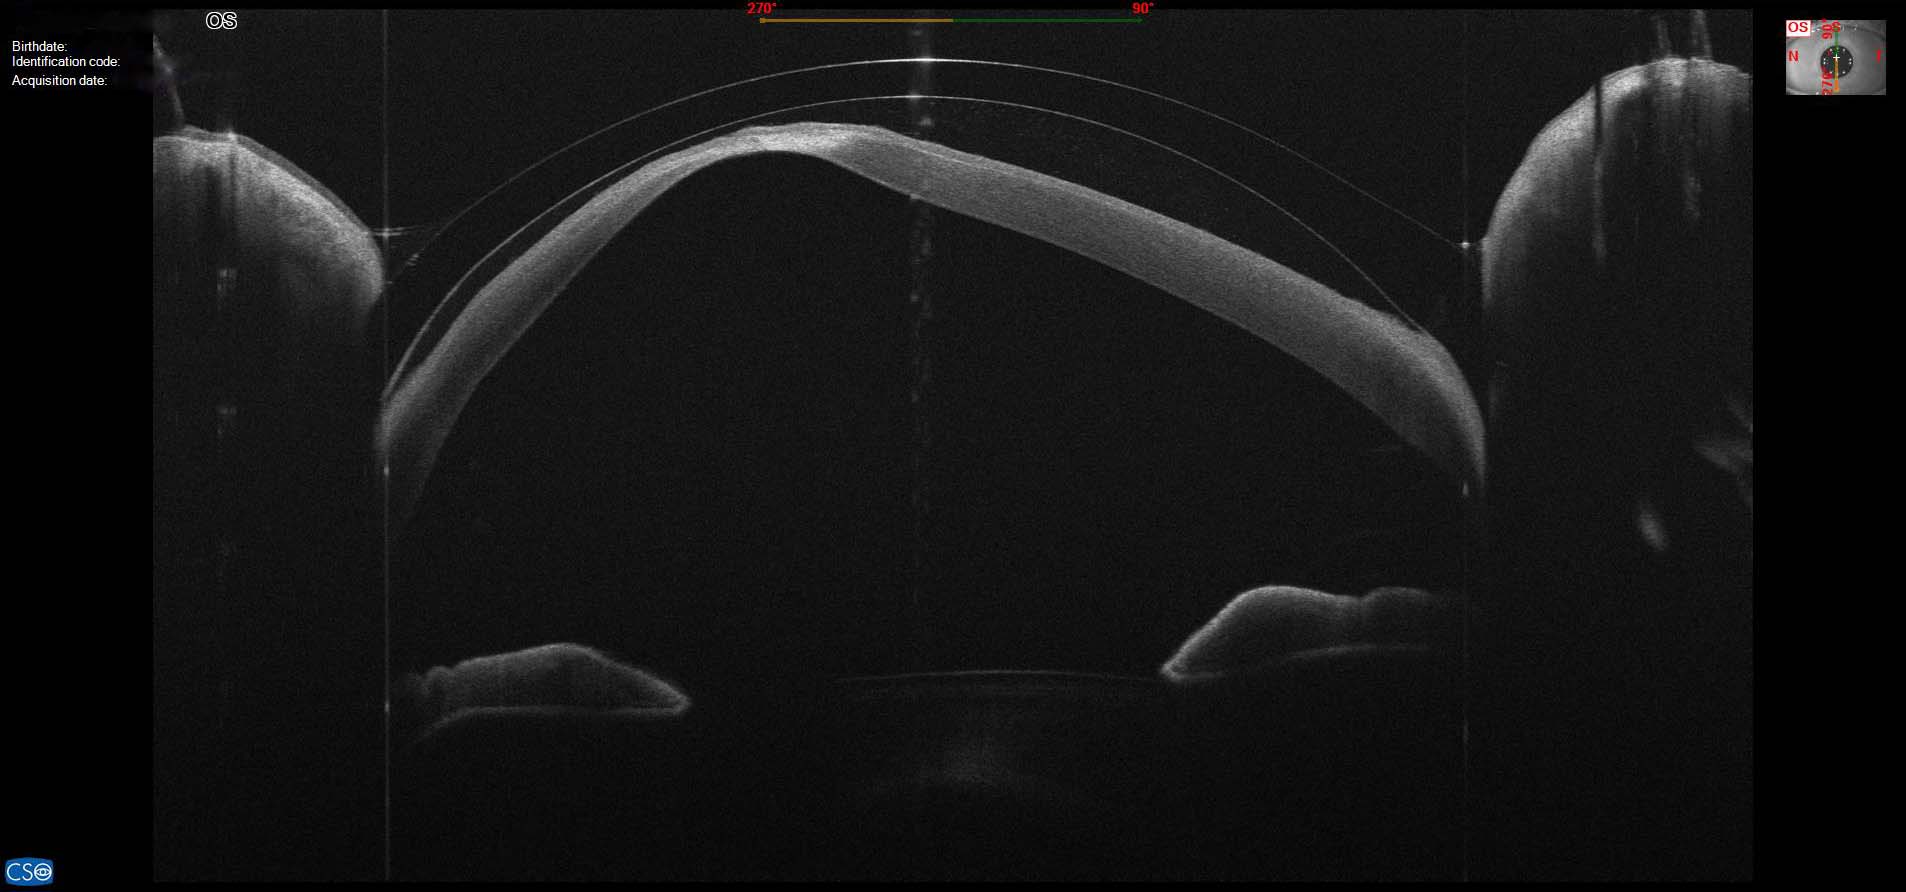

Scleral Contact Lens For Keratoconus . The most used keratoconus lens is called a scleral contact lens. Contact lens (cl) application has a primary place and importance in the correction of the optic problems due to the disease. Scleral lenses are larger than your cornea, so they completely vault over the “cone,” making a new, smooth surface for light to focus on. Scleral contact lenses for keratoconus. As the condition progresses, specific contact lenses, including hard (rgp) or scleral lenses, are essential to compensate for the new irregular shape of the cornea and improve vision clarity. When keratoconus is advanced, scleral lenses are often the preferred kind of contact lens. Many eye care professionals recommend scleral contact lenses for a variety. Scleral lenses rest on the sclera and vault over the cornea, offering greater comfort than traditional rgp or hard lenses. In its early stages, kc is generally treated with glasses or contact lenses to improve vision clarity. They offer good comfort, especially if your eyes are very sensitive. Technological advances have refined the fitting and customization of scleral lenses for keratoconus, emphasizing precision.

They offer good comfort, especially if your eyes are very sensitive. Contact lens (cl) application has a primary place and importance in the correction of the optic problems due to the disease. Scleral lenses rest on the sclera and vault over the cornea, offering greater comfort than traditional rgp or hard lenses. As the condition progresses, specific contact lenses, including hard (rgp) or scleral lenses, are essential to compensate for the new irregular shape of the cornea and improve vision clarity. When keratoconus is advanced, scleral lenses are often the preferred kind of contact lens. In its early stages, kc is generally treated with glasses or contact lenses to improve vision clarity. Technological advances have refined the fitting and customization of scleral lenses for keratoconus, emphasizing precision. Many eye care professionals recommend scleral contact lenses for a variety. Scleral contact lenses for keratoconus. Scleral lenses are larger than your cornea, so they completely vault over the “cone,” making a new, smooth surface for light to focus on.